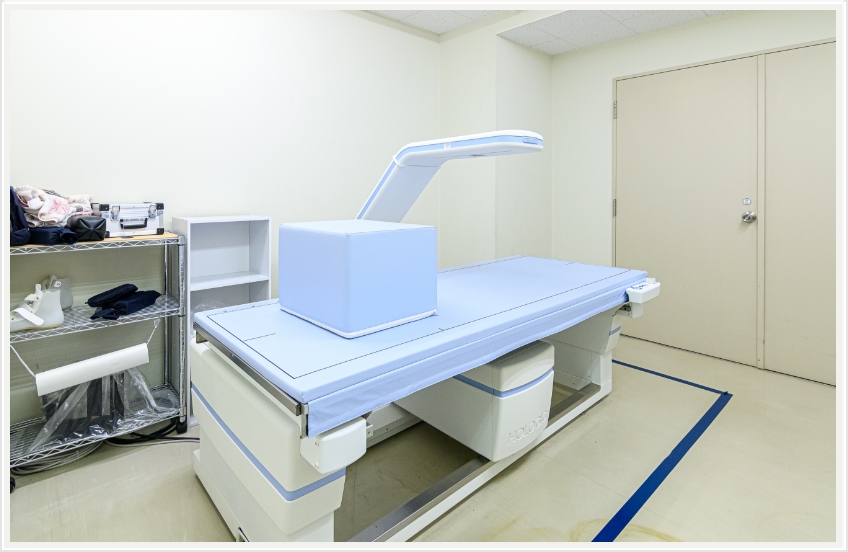

骨密度測定検査(DXA)

骨密度測定検査とは

体の中の腰椎等の骨密度を弱いX線を使用して非侵襲に測定し、骨粗鬆症の診断や、その経過観察に有用な情報をもたらす検査法です。

検査所要時間は10分程度で、検査による痛みはございませんので安心して検査をお受け下さい。

装置・機器紹介